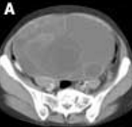

Mucinous Cystadenoma

Jinichi Tokeshi, MD; John M. Nakayama, MS

<div id="article-content-body"> <p><img alt="" src="http://imaging.cmpmedica.com/consultantlive/images/articles/2007/01052007/0705ConPCCystB_thumbnail.jpg"...